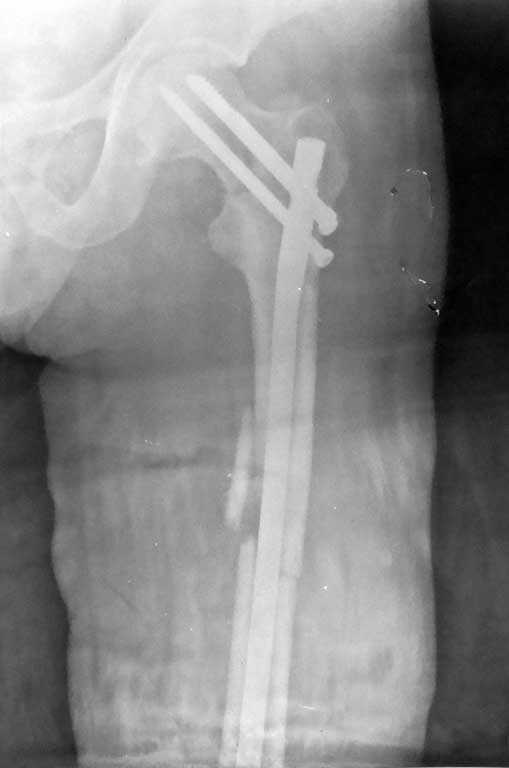

Уважаемые коллеги, на форуме был представлен случай перелома шейки и диафиза бедра, где после БИОС наступил варус шейки и винты упирались в крышу сустава. Форумом было рекомендовано пересинтезировать. Мы пригласили нашего дорогого друга Челнокова А.Н., основоположника БИОС в нашем регионе, который несмотря на очень занятость, и дальность расстояния решил выручать коллег и приехал к нам. Винты из шейки удалены, наложен дистрактор, произведена репозиция шейки, стержень ChM удален, произведен остеосинтез стержнем DePuy, шейка фиксирована, кроме стандартных двух винтов, еще одним винтом спереди стержня. рентген снимки прилагаются.

Поздравляю с удачной работой. Удались репозиция и фиксация!

Для профилактики осложнений рекомендуется фиксировать отдельными фиксаторами для каждого перелома, например: DHS и ретроградный гвоздь. Но современные трохантерные гвозди, например VERSANAIL, дают возможность фиксировать одним фиксатором шейку и диафиз. И учитывая, что с момента первичной фиксации диафиза прошло более двух месяцев, можно рекомендовать нагрузку Weight Bering As Tolerated, т.е. можно нагружать конечность, как сможет.